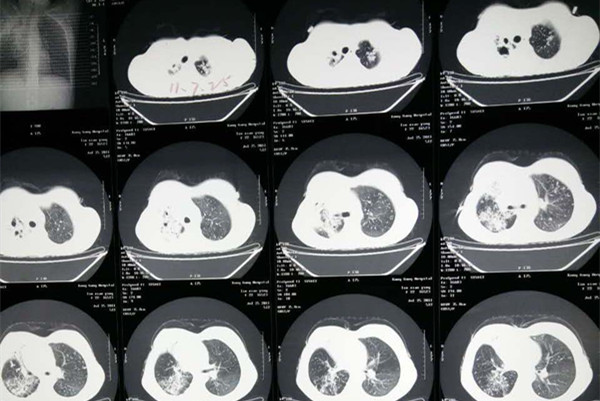

结核性胸膜炎是由结核菌及其代谢产物,进入高度敏感状态的机体胸膜腔而引起的胸膜炎症,临床将其发病类型分为了三种即干性胸膜炎、渗出性胸膜炎和结核性脓胸,各类型表现症状不一。目前对于该病治疗主要推荐的是抗结核药物治疗,但是通过治疗现状来看,抗结核药物治疗效果不是特别理想,经常会导致耐药的出现,所以今天关于结核性胸膜炎耐药怎么治疗,将是本篇的重点分享内容。